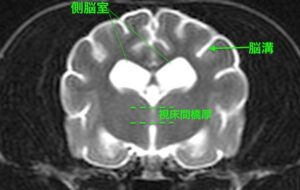

![[横断像(本症例)、T2強調画像]](https://saitovet.com/wp-content/uploads/2025/11/2-300x190.jpg)

右画像の若齢犬と比べてみると、

・脳のしわの部分(脳溝)が分かりやすい

・脳の外側と内側(灰白質と白質)の境目が分かりにくい

→脳の萎縮が疑われる

しかし本症例ではこれは異常ではなく、年齢的に正常な加齢性の脳萎縮であると判断できる。

本症例はMRI検査と脳脊髄液(脳や神経の周りを囲む液体)の検査で、加齢性の変化以外の異常が認められませんでした。